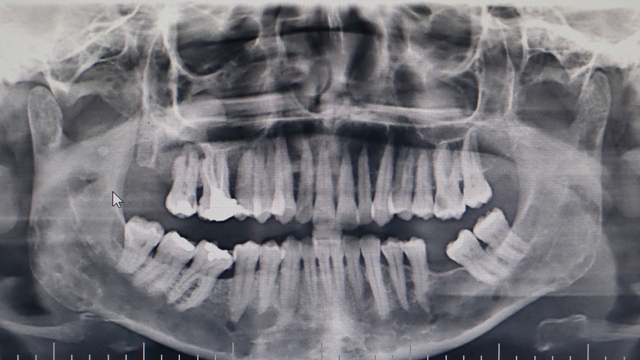

OMÜ Diş Hekimliği Fakültesi Dekanı Prof. Dr. Kaan Gündüz, vatandaşların ağız içi yaraları çoğu zaman önemsemediğini, tütün kullanımı, yetersiz ağız bakımı, güneş maruziyeti ve HPV virüsünün ağız kanserlerinin artışında etkili olduğunu ifade etti. Ağızda 2 haftadan uzun süren yaralar, sebepsiz diş sallanması, uyuşukluk ve çene ağrıları mutlaka dikkate alınması gerektiğini belirten Prof. Dr. Gündüz, ağız kanserinden korunma yolları arasında tütün ve alkol kullanımını azaltmak olduğunu belirtti. Prof. Dr. Gündüz, “Oral kanserler dediğimiz şey aslında başlangıçları çok hızlı ve sinsi gelişen durumlar. Bundan dolayı mutlaka hastaların 2 haftadan uzun süren ağızdaki yaraları eğer mevcutsa en yakın diş hekimlerine başvurmaları gerekmekte. En son yapılan, 2022 yılında Sağlık Bakanlığı yapmış oldu araştırmada 2 bin 246 tane ağız kanserine rastlanmış. Bu vakaların 551 tanesi ölümle sonuçlanmış. Bu da Türkiye kanser görülme olasılığını yüzde 1'ine tekabül ediyor ama şimdi şöyle bir durum var. Şimdi bizim insanlarımız kulağından bir damla kan gelince hemen işte gerekli doktora gider iken ağzından kan gelme durumunda çok fazla önemsemiyor. Yani ağız, dişler çok fazla önemsemiyor ne yazık ki. Ancak Özellikle son yıllarda artan tütün kullanımı ki bunun formasyonları var biliyorsunuz işte ne bileyim nargilesinden, piposundan, purosundan artmasından dolayı oral hijyenin, ağız bakımının eksikliğinden dolayı ve son yıllarda özellikle sizlerin de televizyonlarda veya işte bazı haber kanallarına duyduğunuz Human Papilloma Virüsü dediğimiz HPV'nin yaygınlaşmasından dolayı güneşe maruziyetinden dolayı insanlarda özellikle oral kanserler çok daha fazla sıklıkla görülüyor” diye konuştu.

Ağız kanserinde erken tanı gerçekleşirse hastaların ölümle sonuçlanmasının önüne geçilebileceğini ifade eden Prof. Dr. Gündüz, “Biz kurum olarak Karadeniz'in en büyük üniversitesiyiz ve de fakülte olarak da Karadeniz'de büyük bir hizmet vermekteyiz. Ortalama yaklaşık günde 500 hasta, aylıkta 10 bine yakın hasta bakıyoruz. Biz yapmış olduğumuz seminerlerde hem öğrencilerimizi hem asistanlarımızı hem de halkımızı bu konuda bilgilendirmeye çalışıyoruz. Erken tanı eğer gerçekleşirse bu hastalıkların ölümle sonuçlanmasının nispeten önüne geçmiş oluyoruz. Çünkü erken tanı biliyorsunuz her kanser vakasında çok önemli bir yer tutmakta. Herhangi birisi ağzında eğer 2 haftanın üzerine geçmeyen bir yara varsa mutlaka en yakın diş hekimine başvurması gerekmekte. Sebepsiz yere dişlerin sallanması, uyuşukluk olması, yüzde sebepsiz ağrıların, çene bölgesinde sebepsiz ağrıların oluşması kanserlerin başlangıç bulguları arasındadır. Zaten kanserlerin en fazla oluştuğu yerler ağız içerisinde dilin özellikle arka kenarlarıdır. Bunlar ne yazık ki başlangıçları da ağrısız olduğu için bir kısmının gözden kaçabilmekte. O yüzden insanlarımızdan, halkımızdan bu konuda dikkat etmeleri, eğer böyle bir lezyonla muhatap olurlarsa mesela bir yakınından ağız içerisindeki görüntüsünü çekmesini talep etmeli. 2 hafta sonra da aynı şekilde bu görüntü duruyorsa veya daha da büyümüşse en yakın merkeze gitmesini önermekteyiz” ifadelerini kullandı.